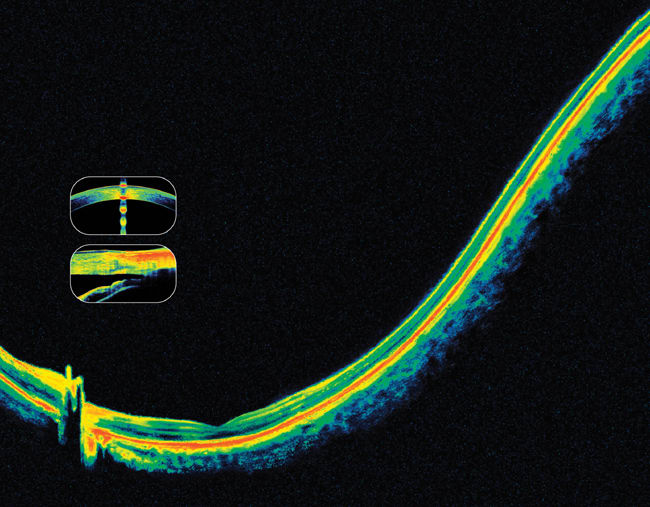

MAIN IMAGE ADAPTED FROM RETINAL OCT; DIGITAL ILLUSTRATION BY JOEL & SHARON HARRIS. INSET IMAGES DEPICT POST-LASIK CORNEA (TOP) AND NARROW ANGLE (BOTTOM), COURTESY OF DAVID HUANG, MD, DOHENY EYE INSTITUTE, LOS ANGELES.

FD-OCT provides highly detailed images of anterior (left) and posterior (right) structures. RTVue scans courtesy of David Huang, M.D.